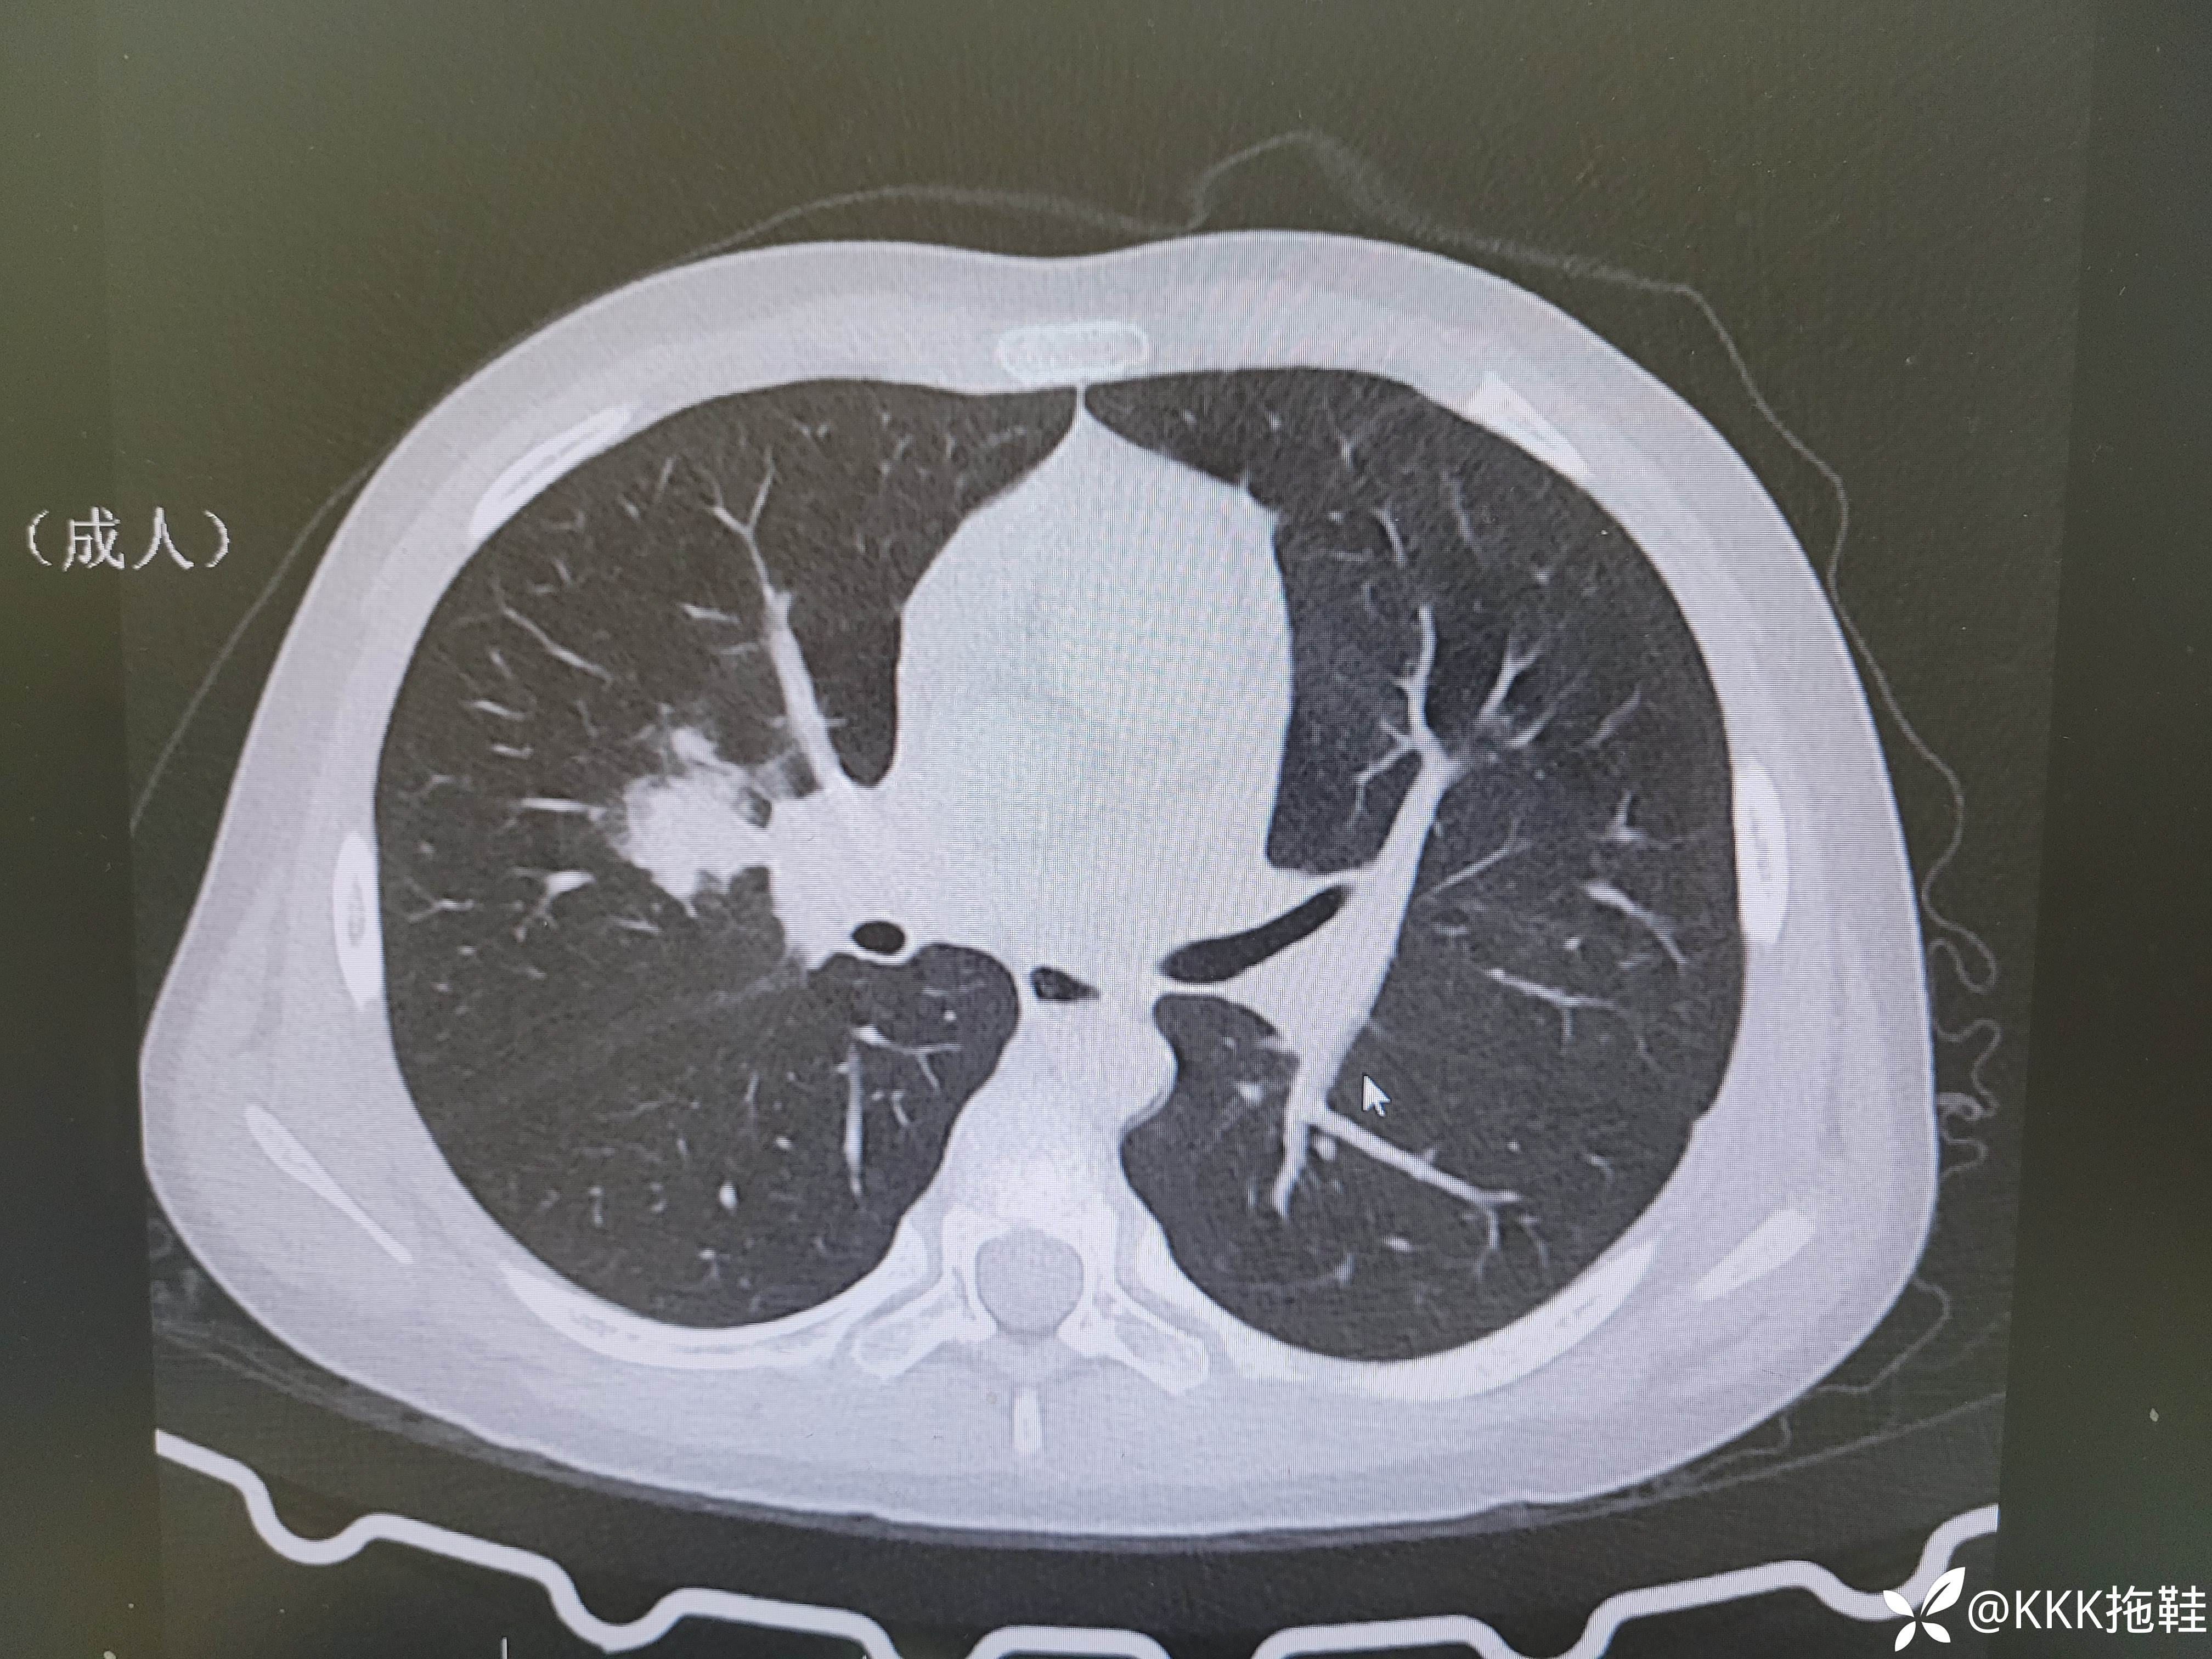

入院当天CT